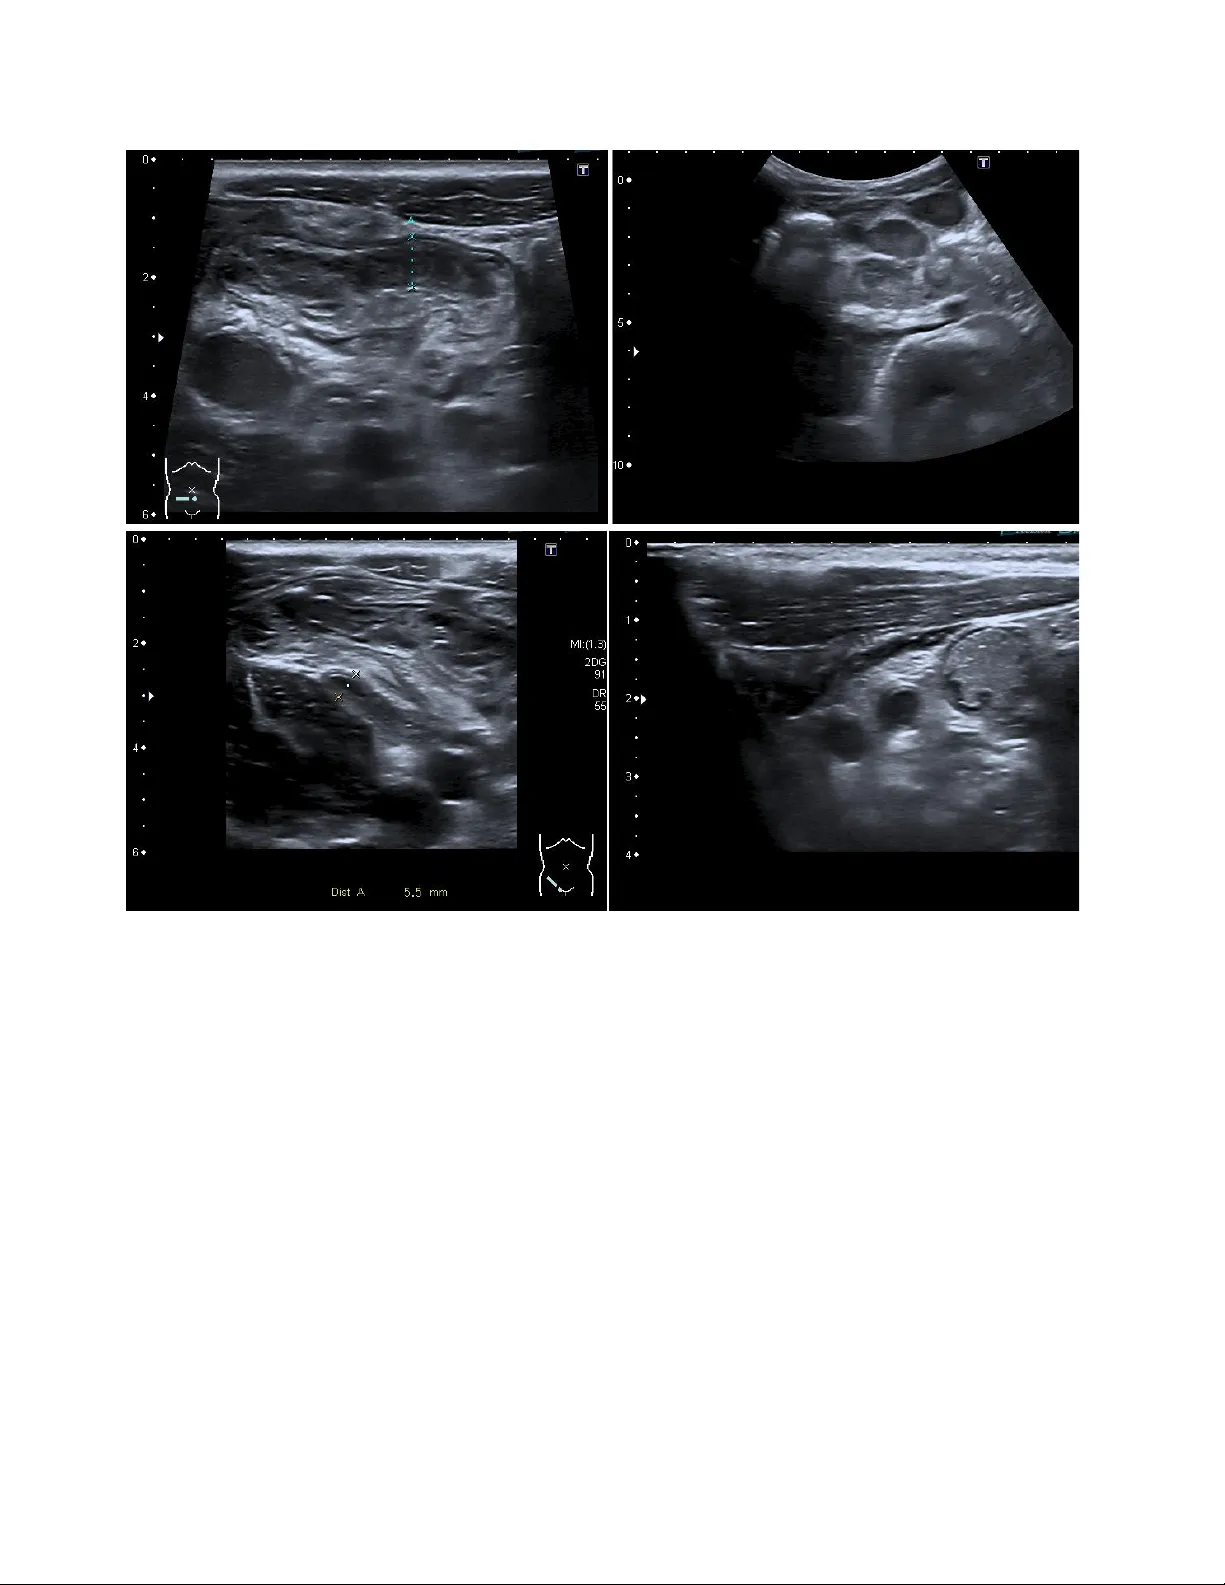

이 논문은 소아 복통 환자에서 초음파 영상만으로 충수염을 판별하는 자동화된 진단 시스템을 제안한다는 점에서 임상적·기술적 의미가 크다. 데이터는 독일 Regensburg 소아 충수염 데이터셋으로, 1~15장의 오른쪽 하복부 초음파 영상을 포함한 1,200여 명(정확한 수는 논문에 명시되지 않음)의 환자 데이터를 활용하였다. 각 영상은 충수, 림프절, 주변 조직을 포함하며, 영상 품질이 환자 연령·체형·스캔 조건에 따라 크게 달라지는 것이 특징이다.

전처리 단계에서는 먼저 DICOM 혹은 PNG 형식의 원본 영상을 0~1 범위로 정규화하고, ResNet 입력 크기에 맞추어 224×224 픽셀로 리사이징하였다. 이후 랜덤 회전·수평·수직 뒤집기·밝기·대비 변환을 통해 데이터 증강을 수행했으며, 이는 특히 소아 초음파의 스페클 노이즈와 저대비 특성을 보완하는 데 기여한다.